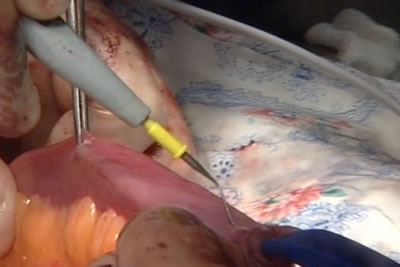

Линейкой оператор отмеряет нужный участок тонкого кишечника

для мочевого резервуара.